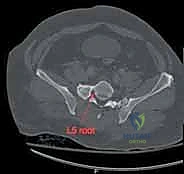

يمر عبر عظم العجز جذور الأعصاب العجزية التي تتحكم في وظائف حيوية مثل حركة الأطراف السفلية، التحكم في المثانة، ووظائف الأمعاء. أي انزياح عظمي في هذه المنطقة قد يؤدي إلى قطع أو انضغاط هذه الأعصاب، مما يسبب إعاقة دائمة إذا لم يتم تحريرها وتثبيت الكسر بدقة متناهية بواسطة خبير مثل الأستاذ الدكتور محمد هطيف.

3. التصوير المقطعي المحوسب (CT Scan): وهو المعيار الذهبي (Gold Standard) لتشخيص كسور الحوض والعجز. يقوم الدكتور هطيف باستخدام تقنية إعادة البناء ثلاثي الأبعاد (3D Reconstruction) لفهم هندسة الكسر بدقة متناهية قبل الدخول إلى غرفة العمليات.